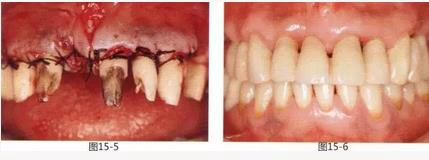

圖13-3   26歲,女性。由其他診所介紹而來。右上橋體部的基底容易滯留食物殘渣。

圖13-4  在形成唇側齦瓣時,發(fā)現(xiàn)右上2根尖對應位置有牙間囊腫造成的牙槽骨缺失。